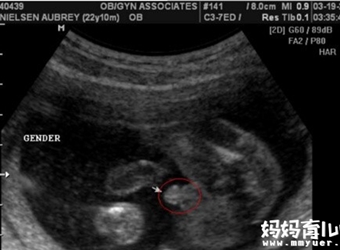

四维彩超怎么分辨男女?据称,在彩超单上会印,顶头最右边有两行字,是英文字母和数字组成的,第一行是日期,第二行是时间,如果第一行是M开头,那就是male男…

看着宝贝一切都很正常,我激动的哭了,哈哈哈。。。。特别是上来的那张小鸡鸡的图片,课清晰了,那个医生都说好清晰啊,哈哈,医生很厉害,她取的那个角度就是…